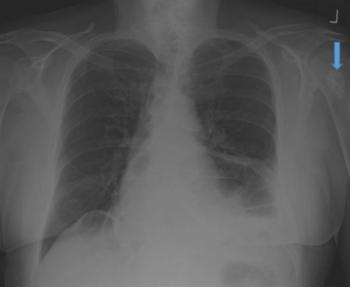

Chest x-ray in an older man confirmed a diagnosis of pneumonia but revealed an asymptomatic lesion in the left humerus. What is in the differential?